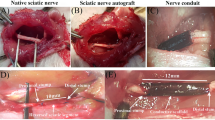

Based on the results of the above physical and biological properties of the scaffolds, 7CS/3SF scaffold was selected to regenerate the sciatic nerve across a 10-mm long surgically induced sciatic nerve injury in a rat model. Briefly, 32 female Sprague-Dawley rats (200–230 g) were used to evaluate the nerve regeneration in 7CS/3SF scaffold. The animals were randomly divided into four groups: (1) the SC-7CS/3SF scaffold group (n = 8); (2) ADSC-7CS/3SF scaffold group (n = 8); (3) 7CS/3SF scaffold group (n = 8); (4) the non-grafted rats as a negative control group (n = 8). For the surgical procedures, the animals were anesthetized by administering 10% chloral hydrate (0.35 ml/100 g) intraperitoneally (i.p.) and the left sciatic nerve was exposed through a skin incision extending from the greater trochanter to the mid-thigh followed by splitting the overlying gluteal muscle. The nerve injured model was performed by half sectioning the exposed sciatic nerve through a fine scissor cut every 2 mm within 1 cm as shown in Fig. 1c. The injured sciatic nerve was then enwrapped by the splitted nerve conduits with 10-0 nylon sutures as shown in Fig. 1e. For the negative control group, the nerve defect was left uncovered. Finally the muscle layer was anastomosed with 4-0 nylon sutures, and the skin was closed with 2-0 silk sutures.

After scaffolds were treated with methanol and sodium hydroxide, the sheet structure remained but was more compact (Fig. 5a–c). All three conduit types possessed a well defined and integrated sheet structure, and 7CS/3SF is much superior. This sheet formation is the first step towards mimicking the layered basement membrane structure. In addition, fiber-like morphology was observed on the interior surface of the conduits with increasing of SF concentration (Fig. 5d–f).

Complications related to surgical procedures did not occur. Wounded tissues spontaneously healed and there were no trophic ulcers on operated limbs or experimental animal fatalities. Following surgery, locomotor functions were completely absent in operated limbs. Palms on the operated side of rats could not touch the ground while walking. A small number of animals in the negative control group had shown a tendency to auto-mutilate treated digits and some mutilated the entire forefoot. After 24 weeks, both the SCs-7CS/3SF and ADSCs-7CS/3SF grafted rats were able to grasp a grid (Fig. 7a, b) and coordinate their movement with each other. Operated limb strengths appeared approximately equal to contralateral limbs. Locomotor recovery of the 7CS/3SF scaffold group was less than that of the ADSCs-7CS/3SF scaffold group (Fig. 7c), but more than that of the negative control (Fig. 7d). In the negative control, operated hind limbs demonstrated limping, gastrocnemius muscle atrophy, load-bearing incapacity and uncoordinated motion with unoperated hind limbs (Fig. 7c). Neither scaffold dislocation nor neuroma formation was observed in grafted rats. However, there was loose tissue in the injured segment of the negative control (Fig. 8). Serious adhesion of the injured segment to the epimysium of the underlying musculature was also observed.